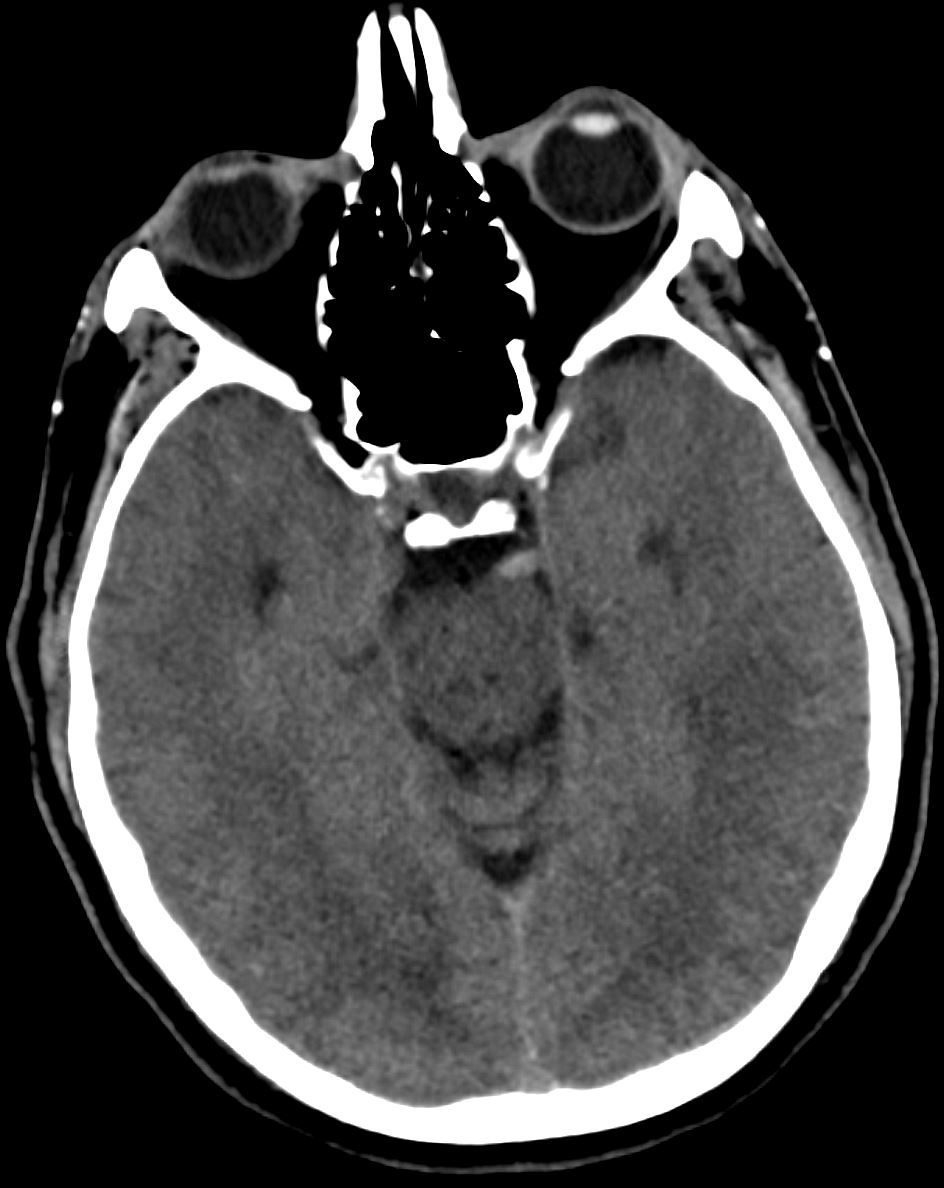

Image IQ Quiz: Middle-Aged Man Presents with Left-Sided Weakness

Middle age male with left sided weakness. What is the most likely diagnosis? What radiology sign is demonstrated?